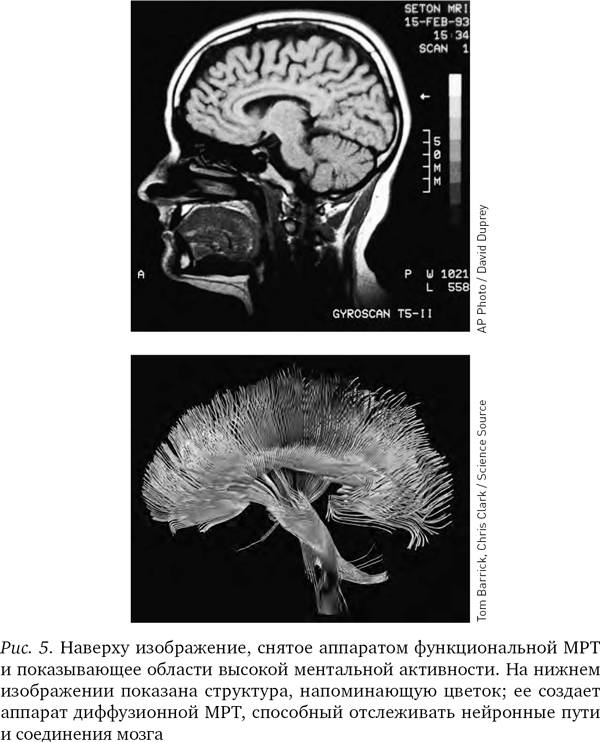

Вначале, когда аппараты МРТ только появились, они могли показывать структуру мозга лишь в статике и на различных его участках. Однако в середине 1990-х гг. был изобретен новый вид МРТ, получивший название функциональной магниторезонансной томографии, или фМРТ; и теперь аппараты уже различали присутствие кислорода в крови в сосудах мозга. (Иногда ученые обозначают маленькой буквой перед аббревиатурой МРТ тип аппарата, но мы будем использовать аббревиатуру МРТ во всех случаях.) На полученных при помощи МРТ изображениях не виден непосредственно ток электричества в нейронах, но поскольку без кислорода нейроны не получат энергии, насыщенная кислородом кровь косвенно указывает на поток электрической энергии в нейронах и наглядно показывает, как различные области мозга взаимодействуют между собой.

МРТ-изображения опровергли представление о том, что мышление сосредоточено в едином центре. Напротив, можно видеть, что в процессе мышления электрическая энергия циркулирует по различным частям мозга. Отслеживая путь, который проходят мысли в голове человека, МРТ-аппараты помогли пролить свет на природу болезней Альцгеймера и Паркинсона, шизофрении и других психических заболеваний.

Серьезным преимуществом МРТ-аппаратов является то, что они могут с высокой точностью выделять крохотные, вплоть до десятых долей миллиметра, участки мозга и рассматривать их отдельно. МРТ-изображение — не просто точки на двумерном экране (пикселы), а точки в трехмерном пространстве (вокселы): в результате исследования мы получаем яркое трехмерное изображение мозга, сложенное из десятков тысяч цветных точек.

Различные химические элементы реагируют на разные частоты радиоволн по-разному, поэтому мы можем, изменяя частоту волны, определять, где какие элементы находятся. Как уже отмечалось, при фМРТ в основном отслеживаются атомы кислорода в крови и измеряют кровоток, но вообще-то аппарат МРТ можно настроить на любое вещество. В последнее десятилетие появилась новая разновидность МРТ — диффузионно-тензорная; она отслеживает движение воды в объеме мозга. Вода в мозге следует по нейронным путям, поэтому диффузионно-тензорная томография позволяет получить красивые картинки, напоминающие переплетение растущих в саду лиан. Теперь ученые могут мгновенно определить, как части мозга связаны между собой.